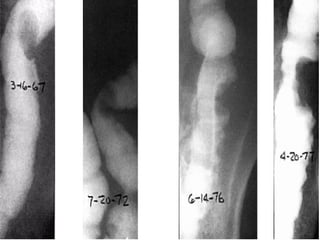

 Colon por enema.

CANCER DE COLONY RECTO DIAGNOSTICO  Historia clínica.  Exploración física ( tacto rectal ).  Laboratorio clínico y Rx. tórax, MT ( ACE ).  Colon por enema.  Colonosocopia ( biopsia ).  TAC  Ultrasonido endoluminal.